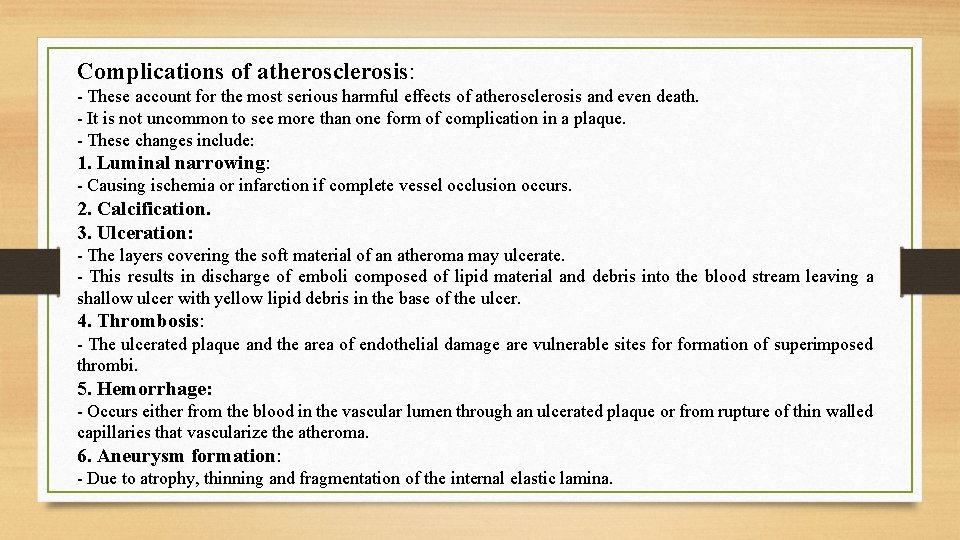

Complications of atherosclerosis: - These account for the most serious harmful effects of atherosclerosis and even death. - It is not uncommon to see more than one form of complication in a plaque. - These changes include: 1. Luminal narrowing: - Causing ischemia or infarction if complete vessel occlusion occurs. 2. Calcification. 3. Ulceration: - The layers covering the soft material of an atheroma may ulcerate. - This results in discharge of emboli composed of lipid material and debris into the blood stream leaving a shallow ulcer with yellow lipid debris in the base of the ulcer. 4. Thrombosis: - The ulcerated plaque and the area of endothelial damage are vulnerable sites formation of superimposed thrombi. 5. Hemorrhage: - Occurs either from the blood in the vascular lumen through an ulcerated plaque or from rupture of thin walled capillaries that vascularize the atheroma. 6. Aneurysm formation: - Due to atrophy, thinning and fragmentation of the internal elastic lamina.